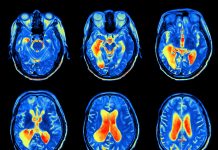

脳活動を画像化するfMRIをAI手法で解析することで、アルツハイマー病および軽度認知障害(MCI)を診断する試みがある。その中でブレイクスルーとも言えるほど極めて高い精度を達成したディープラーニングモデルが、リトアニア・カウナス大学の研究グループによって発表された。

カウナス大学のリリースでは、学術誌 Diagnosticsに発表された同研究を紹介している。18層の畳み込みニューラルネットワーク「ResNet-18」は、61,502の画像データによってトレーニングされており、論文中の検証では、138名のfMRI画像を複数の認知カテゴリー(健常・MCI・早期MCI・後期MCI・アルツハイマー病、等)に分類した。結果、早期MCIとアルツハイマー病、後期MCIとアルツハイマー病、等の識別タスクにおいていずれも99%を超える超高精度を達成した。

研究チームのひとりであるMaskeliūnas教授は「類似のデータで軽度認知障害を診断する試みは初めてのものではない。しかし今回の最大の成果は、そのアルゴリズムの精度にある」と語る。この結果は必ずしも現実世界での性能を示すものではなく、臨床家がアルゴリズムに「完全に」頼るべきという結論にはならない。だが、今回の獲得知見とその技術は、アルツハイマー病およびMCIの診断支援において大いなる可能性を示したものとなる。